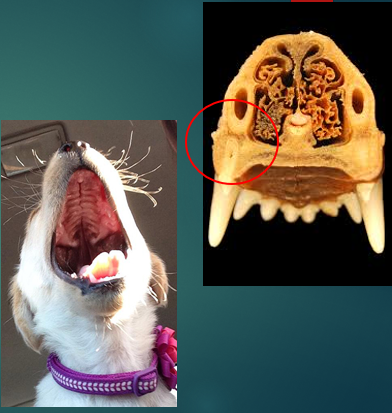

Stenotic nares

Narrowing of the nasal passages, this increases resistance, making breathing in and out more difficult for the paitent

Brachycephalic obstructive airway syndrome

The problems we see in these breeds are the consequences of trying to move air with all this increased resistance. To breathe they need to move O2 through the resp tract to the lungs, these issues with the soft tissues that we’ve highlighted cause resistance to air flow, this then increases Resp effort and rate to get more air in, this increases the negative pressure which makes the issue worse – negative pressure caused by them trying to overcome the resistance means that we get more resistance, more swelling of soft tissues and thus more negative pressure. We will often see abdominal effort with BOAS breathing.

Brachycephalic breeds are prone to becoming hypoxic and overheating ..

When panting air moves over mms and evaporates loose heat – in these animals not as effective, so owners have to be very careful in the heat not to cause heat exhaustion and collapse.